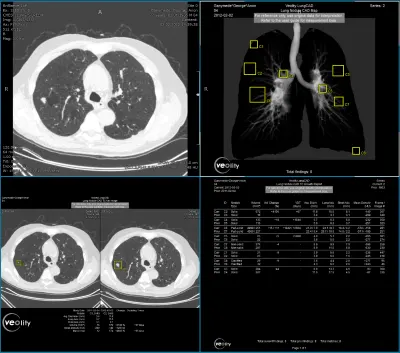

Veolity LungCAD bietet in der Lungenkrebsdiagnostik für Thorax CT-Aufnahmen eine vollständig integrierte KI-gestützte Detektion (CAD) solider Lungenrundherde.

Die Software ermöglicht eine zeiteffiziente und sichere radiologische Befundung von MSCT-Aufnahmen im klinischen Alltag. Veolity LungCAD verbessert die diagnostische Qualität in der Lungendiagnostik und macht komplexe Verlaufskontrollen einfach und effizient. Die besonders praktische automatische Segmentierung der Lungenrundherde mit Volumenmessung hilft Radiologen, reproduzierbare und vergleichbare Ergebnisse zu erzielen. Die Resultate werden einfach in die bestehende IT-Infrastruktur integriert. Radiologen profitieren von den automatischen CAD-Ergebnissen und behalten gleichzeitig die volle Kontrolle über ihren Diagnoseprozess.